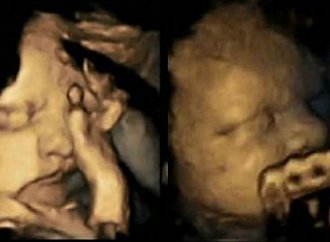

Ce foetus fait la grimace quand sa mère allume une cigarette